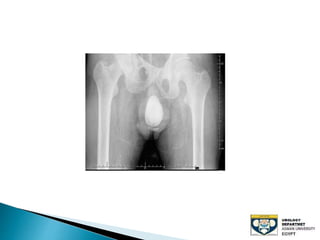

The document discusses urinary tract stones, detailing their types, causes, symptoms, and diagnostic methods. It highlights the risk factors such as infections and obstructions, with men being more commonly affected. Treatment options include various surgical methods, particularly for managing bladder outflow obstruction and lithiasis.